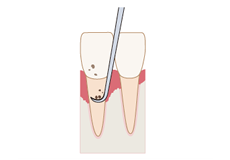

SRP

麻酔をして深いポケット内の歯石を除去し、歯根面を清掃していきます。本数が多い場合は、数回に分けて行います。細菌検査で特定の歯周病菌が検出された場合抗生剤を使った薬物療法を行う場合があります。

手作業の器具による細かな部分の仕上げ

深いところや狭い部分についた歯石を丁寧に取り除ききれいにします。